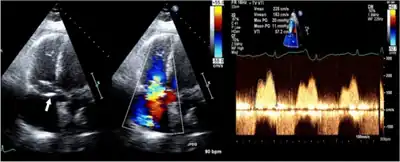

Ultrasound image; 2D and color Doppler in an individual with anti-phospholipid antibody syndrome shows thickening of valve leaflets and continuous-wave Doppler with a mean pressure gradient of 11 mmHg, consistent with severe tricuspid stenosis